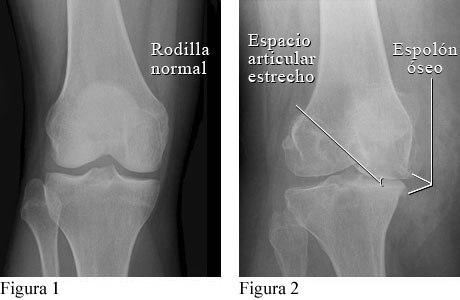

Cortesía de Intermountain Medical Imaging, Boise, Idaho.

La figura 1 es una radiografía de una rodilla normal con espacio normal entre los huesos de la parte superior y de la parte inferior de la pierna. La figura 2 muestra espolones óseos y un estrechamiento del espacio articular causados por osteoartritis.